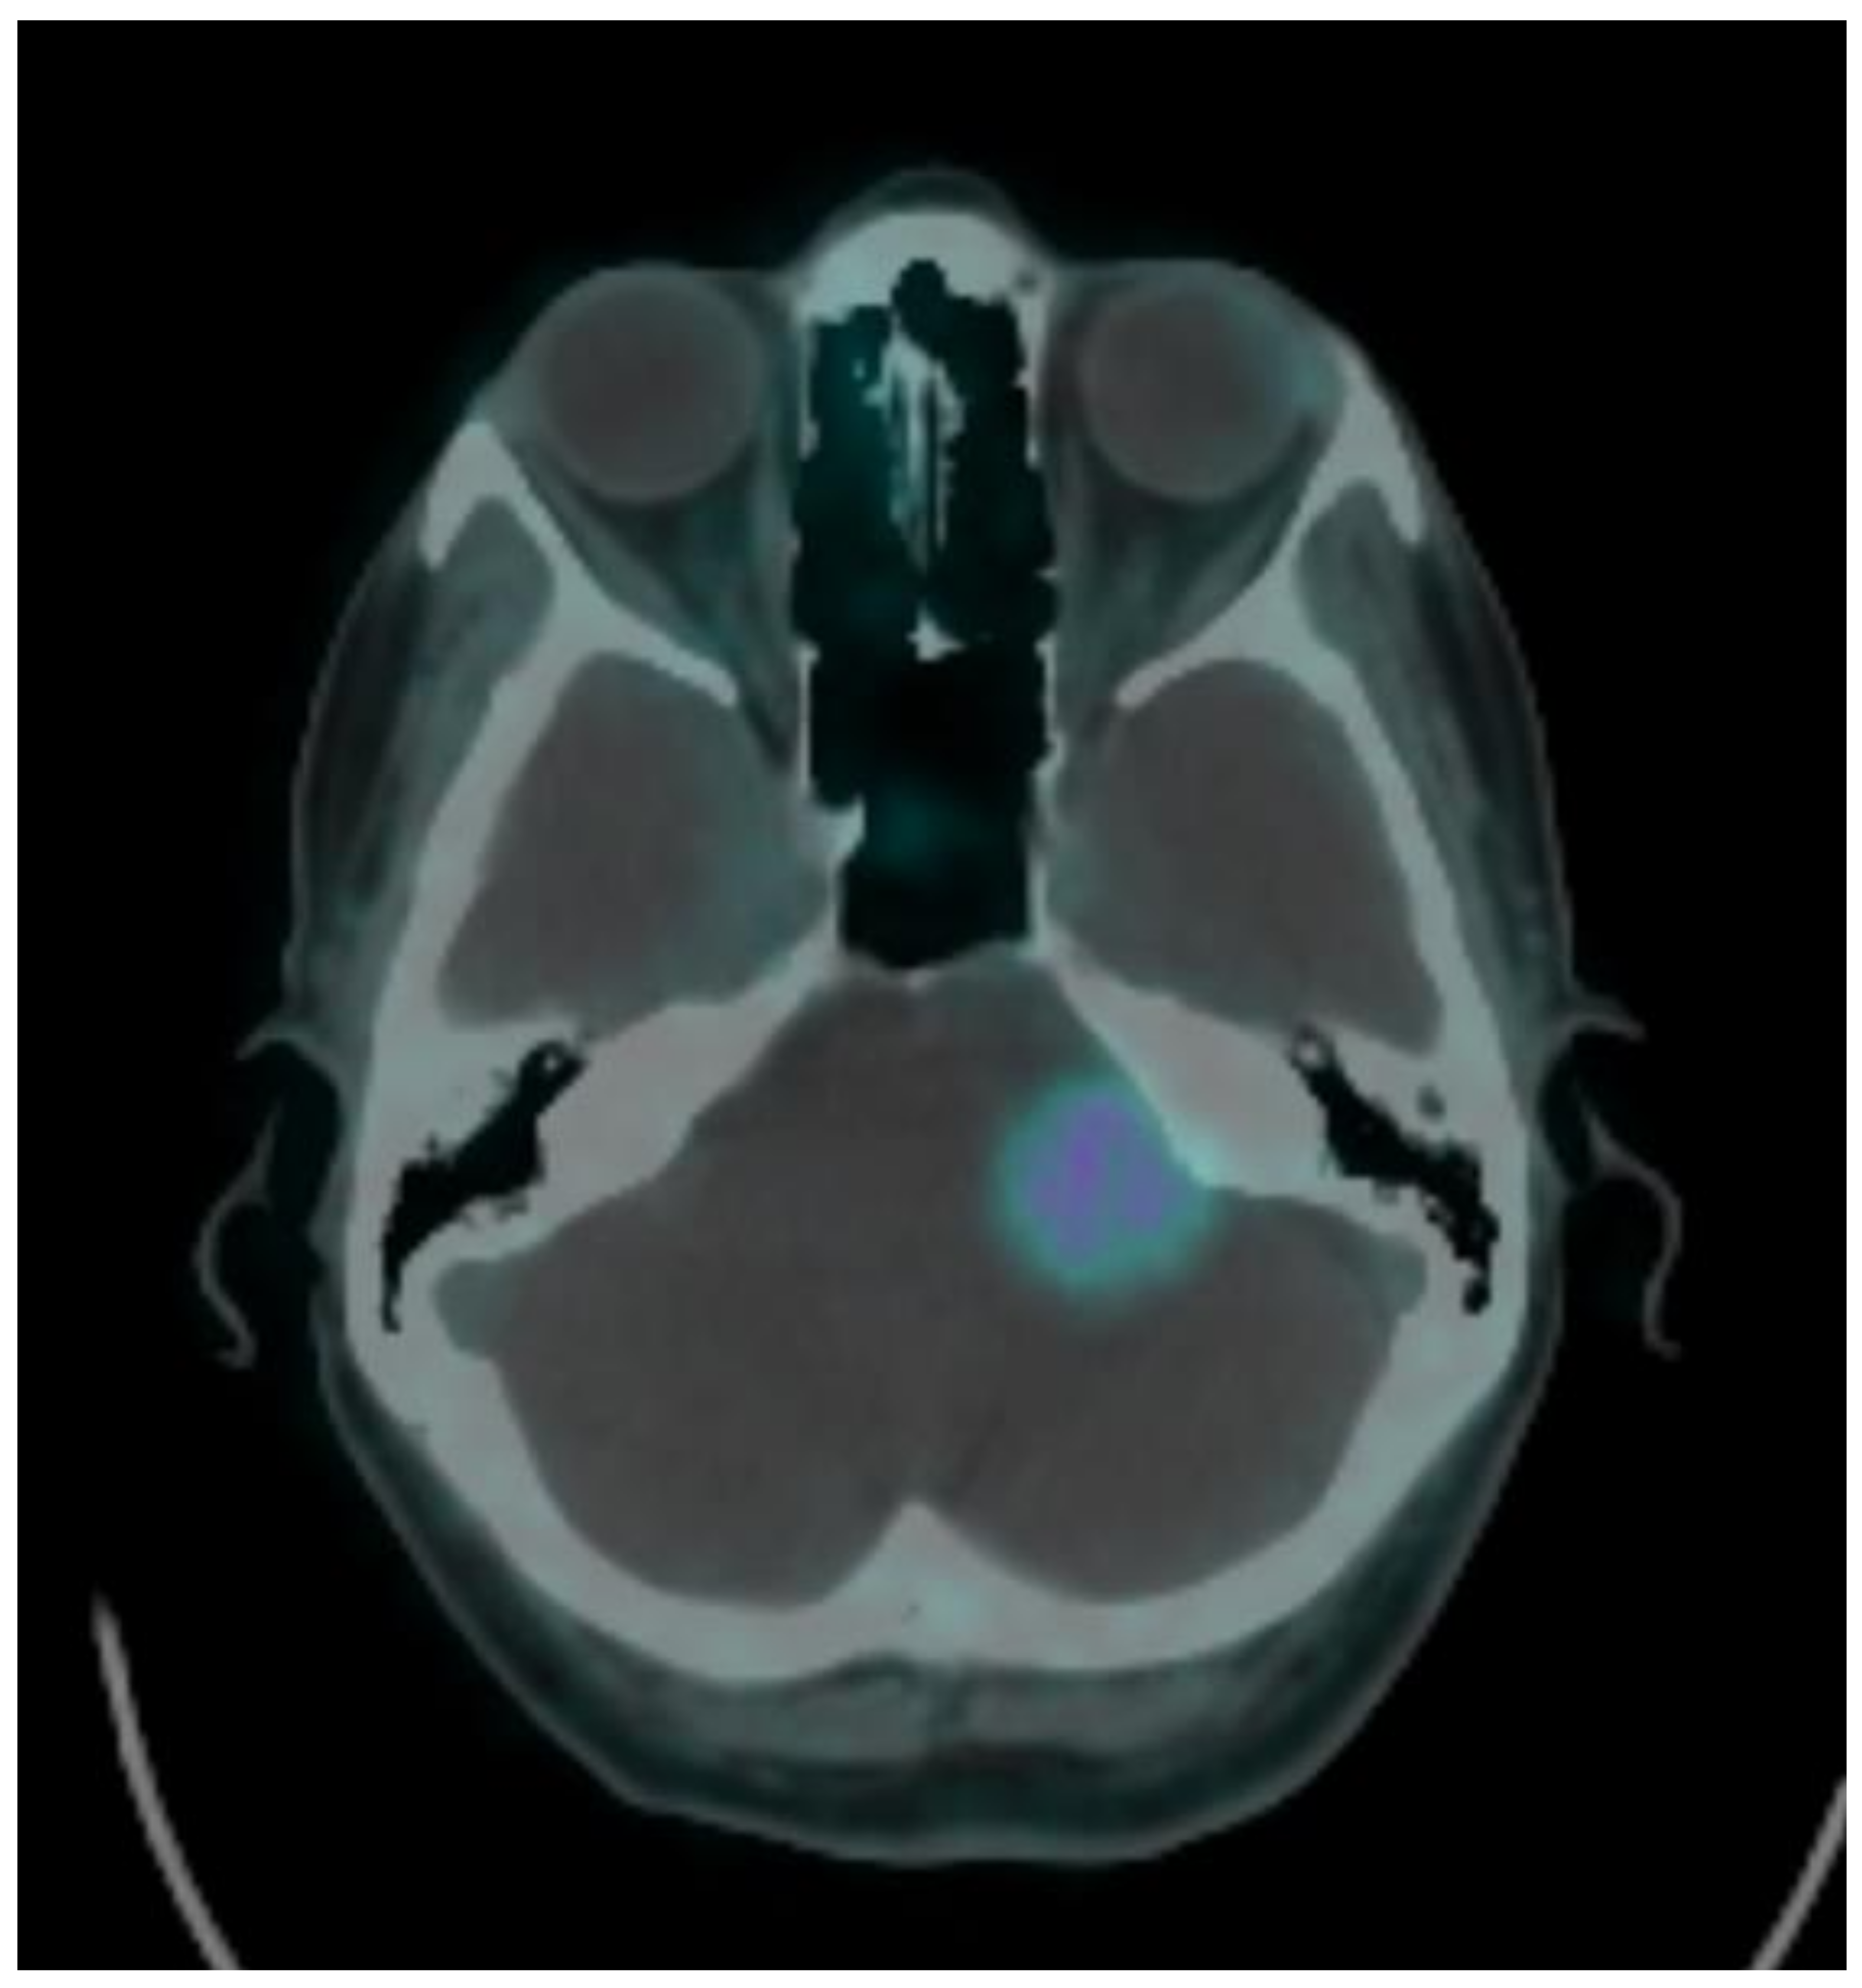

| 2 | 56 | female | left cerebellar | 1.310 | 9.41200765 | 14 | 3.5 | 18 | 2.6 | −26% | 14.0 |

| 16 | 52 | female | left cerebellar | 2.35 | 54.3340367 | 13 | 2.9 | 13.0 | |||